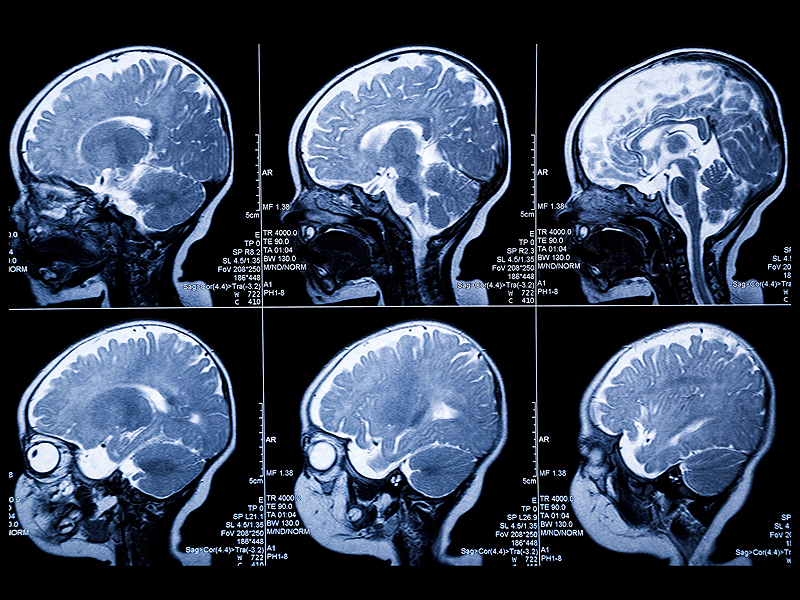

Ils ont réalisé des IRM cérébraux à 6, 12 et 24 mois de vie chez 221 enfants à risque de développement d’un TSA (c’est-à-dire ayant un frère ou une sœur plus âgés atteints) mais également 122 enfants à bas risque (frère ou une sœur plus âgés avec un développement normal). Les auteurs ont développé pour les besoins de l’étude un algorithme mesurant automatiquement le volume du LCR. Le critère de jugement principal (le diagnostic de TSA) était évalué à 24 mois selon les critères du DSM-IV.

Les 47 enfants à risque chez lesquels a été porté un diagnostic de TSA à 24 mois avaient bien une augmentation du volume de LCR dans les espaces sous-arachnoïdien à 6 mois par rapport aux autres enfants à risque et aux enfants à bas risque, y compris après ajustement sur le volume cérébral total (p = 0,0026). Ce résultat était également retrouvé à 12 et 24 mois. En moyenne, les enfants autistes ont un volume de LCR sous arachnoïdien supérieur de 12,20 cm3 par rapport aux autres enfants. Il n’y avait pas de différence entre les enfants à risque indemnes et les enfants à bas risque. De plus, parmi les enfants atteints, les formes plus sévères étaient associées à un volume de LCR sous arachnoïdien plus important (p = 0,02). En pratique, les auteurs calculent que l’utilisation du volume de LCR sous arachnoïdien à 6 mois permet de prédire la survenue d’un TSA avec une sensibilité de 66 % et une spécificité de 69 %.